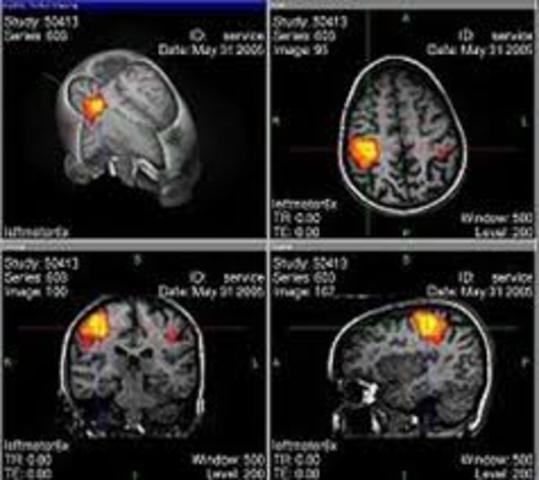

El equipo del Instituto Nacional de Salud Mental identifica las regiones del cerebro que funcionan de manera diferente en personas que sufren dislexia

• Ginebra Edén

Ginebra Edén

Ginebra Edén junto a su equipo de investigación en 1996, utilizó las imágenes de resonancia magnética funcional (IRMF) para poder observar las áreas del cerebro que funcionan de forma distinta en las personas con dislexia.